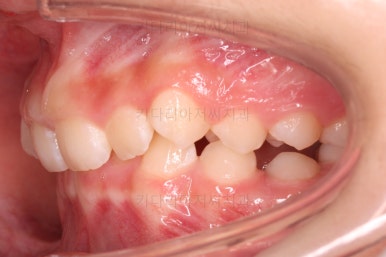

초진 시 입안의 모습입니다.

앞니가 안으로 굽어 들어간 양상인데요. 흔히 "옥니"라고 표현합니다.(뻐드렁니의 반대개념)

오른쪽 상단 사진을 보시면 어금니의 높이와 앞니의 높이가 차이가 많이 납니다.

앞니가 솟구쳐 있는 양상인데요.

그 이유 때문에 어금니로 다물었을 때의 위아래 앞니가 많이 겹쳐서 아래 앞니가 아예 보이지 않는 상황이었어요.

이를 "과개교합"이라고 표현합니다.

그리고 전반적으로 아래 치열이 윗니에 비해 뒤로 밀려 있어서, 어금니의 맞물림이 좋지 못하고 듬성듬성해 보이는 상황이었어요.